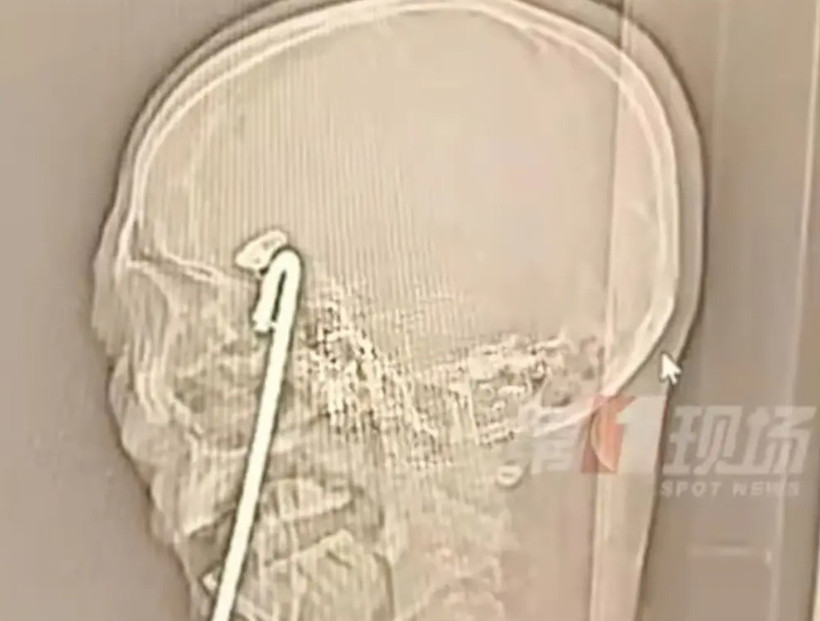

İsmi Aqiang olan bir adam alkolün de etkisiyle dengesini yitirdi ve bir masanın üzerine düştü. Masanın 38 santimetre uzunluğundaki gövdesi adamın kafasına saplandı.

Röntgen görüntülerinde metal parçasının beynin riskli bölgelerine 2 milimetre kala durduğu görülürken ameliyatın başlamasından önce metal parçasının büyük bir kısmını kesmek zorunda kaldı.